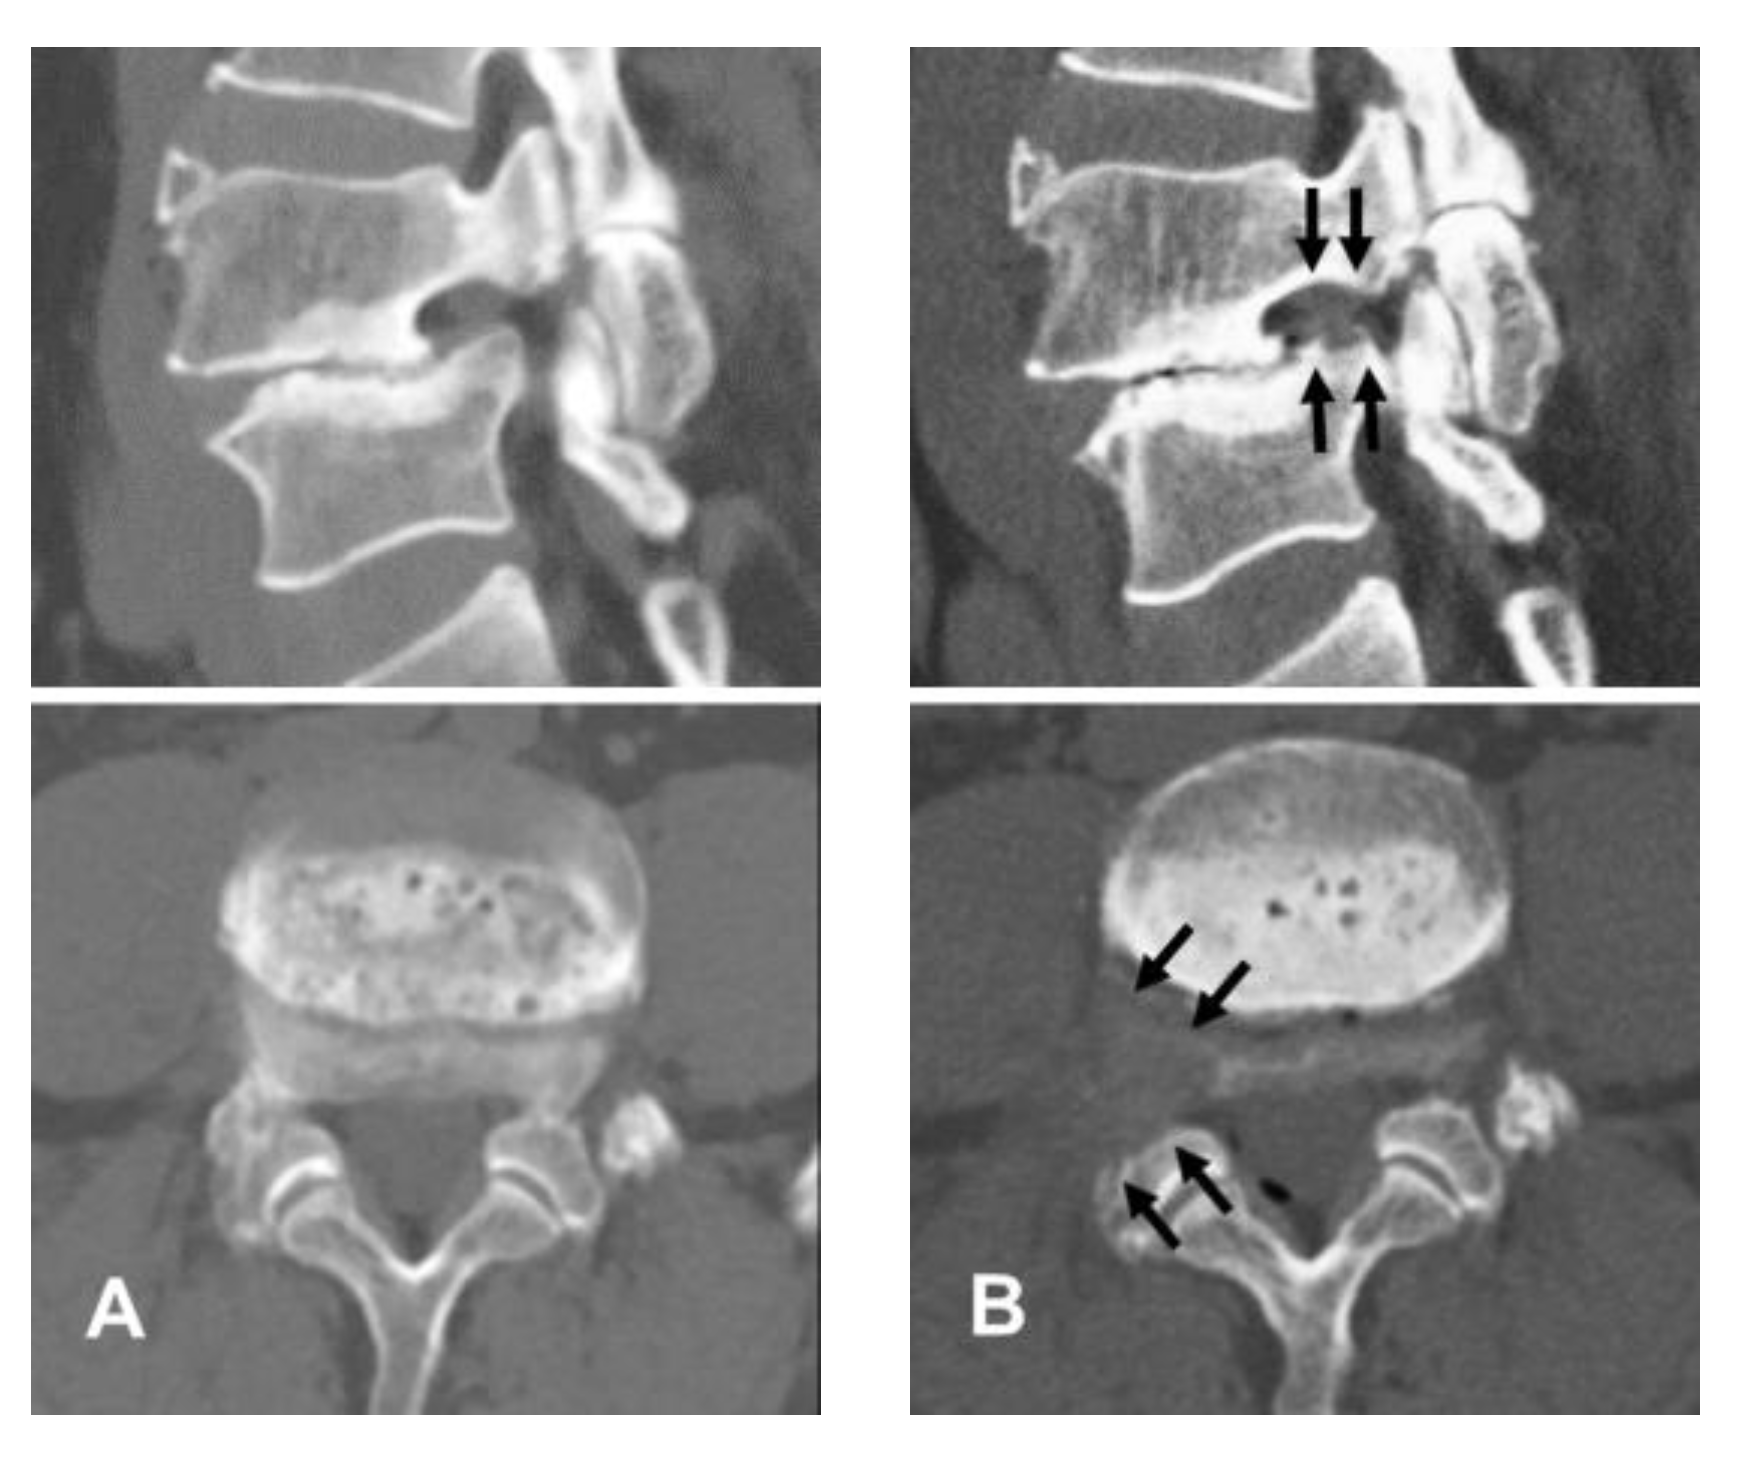

2.1. Patient Evaluation

4.1. Diagnosis and Clinical Outcomes

4.4. Technical Keys Specific to Foraminal Stenosis with Spondylolisthesis